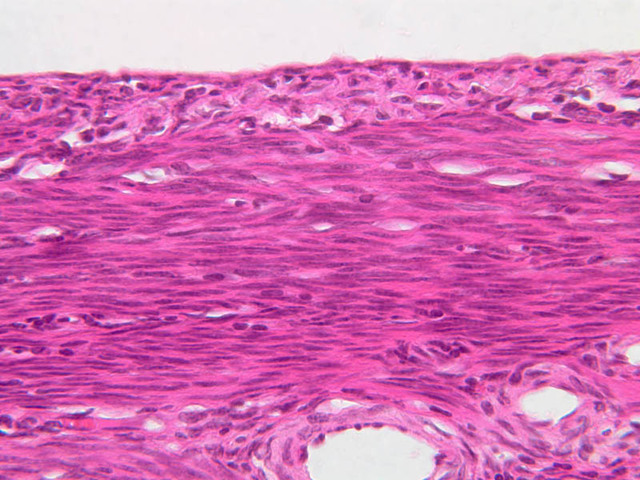

The uterus is a pear-shaped muscular organ, somewhat flattened from front to back. The expanded upper portion is referred to as the fundus, while its lower part, which protrudes into the vagina, is called the cervix. The lumen of the uterus is slit-like and is in communication with that of the uterine tubes (B-97, monkey uterus [1x, 1x, 1x, 1x]). The wall of the uterus consists of three layers: perimetrium, myometrium, and endometrium (B-97 [1x, 1x-labeled] [1x, 1x, 1x]; B-100 [1x, 1x]). The perimetrium is peritoneum which covers the uterus, but is lacking in the posterocaudal third below the peritoneal reflection (B-97 [2.5x, 10x, 20x, 40x]). The myometrium is the very thick middle layer consisting of bundles of smooth muscle cells arranged into several interwoven layers (slide B-93 [1x-labeled, 2.5x] [1x, 2.5x] [1x, 2.5x] [2.5x, 10x, 20x, 40x]). The endometrium is the innermost layer and is a glandular mucosa (B-97 [2.5x, 10x, 20x] [2.5x, 10x, 20x] [2.5x, 10x, 20x, 40x]). It consists of a surface epithelium which is invaginated into tubes called uterine glands. The glands penetrate into a very thick lamina propria referred to as the endometrial stroma. The surface epithelium is a mixture of ciliated and non-ciliated simple columnar cells, whereas the glandular epithelium consists mainly of non-ciliated secretory cells. The endometrial stroma has the appearance of a loose, rather cellular mesenchyme with numerous blood vessels.